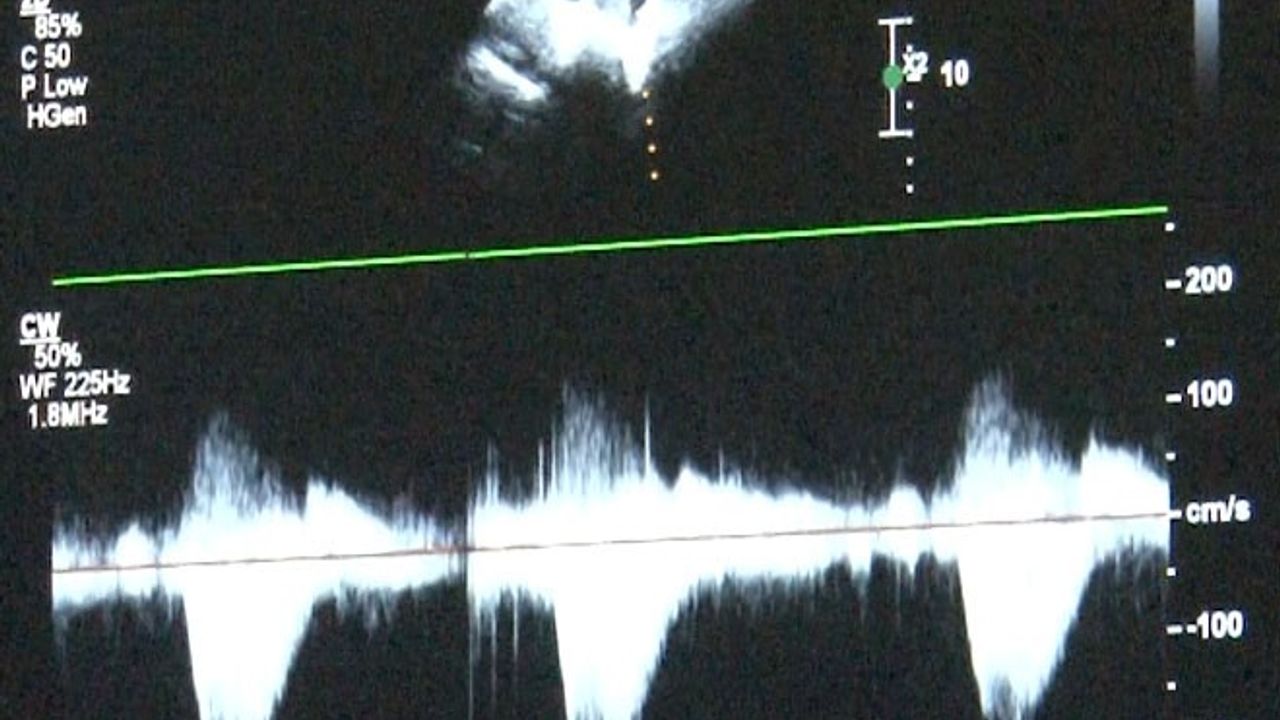

‘Sağlık Bakanlığı verilerine göre her yıl bin canlı doğumdan 8'inde doğumsal kalp hastalığı görebilmekteyiz' diyerek sözlerine başlayan Uzm. Dr. Damla Gökçeer Akbulut, "Yılda 12 bin çocuk doğumsal kalp hastalığıyla dünyaya geliyor. Çeşitli nedenleri olabiliyor bazen annenin gebelikte kullandığı ilaçlar ya da diyabet gibi bir hastalığı olması, genetik rahatsızlıklar, bunlar genetik olarak kalp rahatsızlıklarına yol açabiliyor. Bu hastalarda erken tanı mümkün, daha anne karnındayken fetal ekokardiyografi (anne karnındaki bebeğin kalp yapısını ve işlevini değerlendirmek amacıyla kullanılan bir tıbbi görüntüleme)yle doğumsal kalp hastalığı olan bebeklerde doğum sonrası erken müdahale yapabiliyoruz. Bazı bebekler mor doğabiliyor ancak bazılarında bu bulgular ilk ay içinde gelişebiliyor" dedi.

Uzm. Dr. Gökçeer Akbulut ise, "Ailede daha önceden tanısı olmayan doğumsal kalp hastalığı olan bir bebek olduğunda hızlı nefes alıp verme, morarma ya da emerken soğuk terleme gibi bulgular varsa mutlaka çocuk hekimi kontrolünde bir çocuk kardiyoloğuna hızlıca yönlendirilmesi lazım. Doğar doğmaz müdahale edilmediğinde yaşamsal olabilecek sorunlarla karşılaşabiliyoruz, hasta kaybedilebiliyor. Anne karnında olmuyorsa da doğar doğmaz ekokardiyografi yaparak tanısını koymak mümkün. Hastalarda viral enfeksiyon ve kış döneminde RSV virüsü, ilk 2 yaştaki çocuklarda sık gördüğümüz bir viral enfeksiyon, sezonuna girmiş bulunmaktayız. Doğumsal kalp hastalığı olan çocuklarda ekim, mart ayları arasında mutlaka RSV aşılaması yapılmasını tavsiye ediyorum. İnfluenza dediğimiz belirtiler varsa ya da covid sonrası miyokardit dediğimiz kalp kası iltihabı görebiliyoruz. Çok ciddi boyutlarda şok tablosu dediğimiz tansiyon düşüklüğü, taşikardi dediğimiz nabız hızlanması ve solunum yetersizliği bulguları, hastada ödem artışı, hızlı nefes alıp verme gibi bulgularla yoğun bakım yatışı gerektirebiliyor. Kalp hastası olduğundan emin olduğumuz bir çocukta yıllık aşılamalarına influenza açısından devam edilmesini öneriyoruz" diye konuştu.